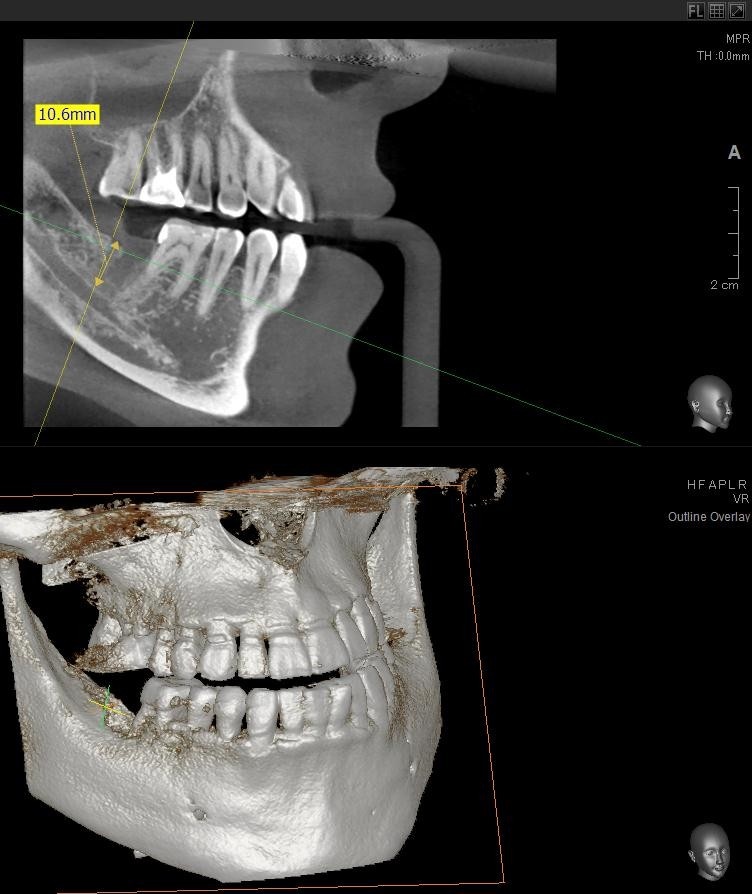

今回の患者様はインプラント植立を希望され、右下7番目の植立が決まりました。

ドリルの先端を細い物から徐々に大きい物に変えながら、植立するインプラント体のネジの部分を除いた胴の部分の太さに合わせた大きさの穴を開けていきます。

開けた穴に、専用道具を使ってネジを締めるように長さ2センチ程のインプラントを骨に埋め込んでいきます。

しっかりとインプラント埋め込まれた後は、動揺がないか、噛んだ時に当たらないかなどを確認して、最後にパノラマ写真を撮影して今回のオペは終了となりました。